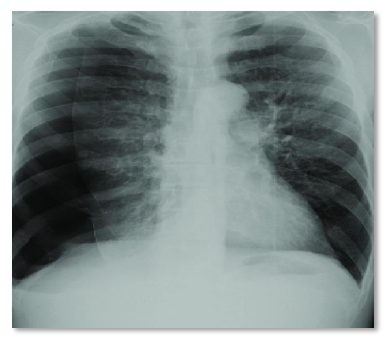

Paciente vítima de politrauma entre carro e moto, no local se levantou, consciente. Após alguns minutos, iniciou quadro de dor torácica, desconforto respiratório, elevação de hemitórax direito, com elevação de cúpula e distensão de veias do pescoço, ipsilateral.

O tratamento correto é: